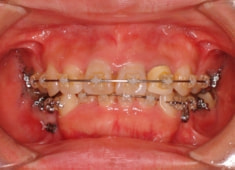

治療開始時